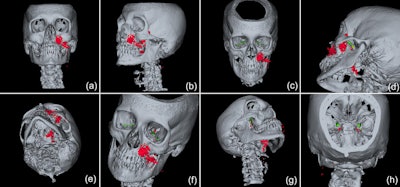

CT scans show that the pterygoid canal (a) and the forum rotundum (b) may be possible entry pathways for the air to enter the intracranial space. This is especially possible within the canal leading to the foramen rotundum, where several smaller air bubbles were captured.

3D reconstructions of the emphysema (red) and the display of the potential pathways to the intracranial space, including along the inferior orbital fissure and via the foramen rotundum (green) and/or via the pterygoid canal (yellow).